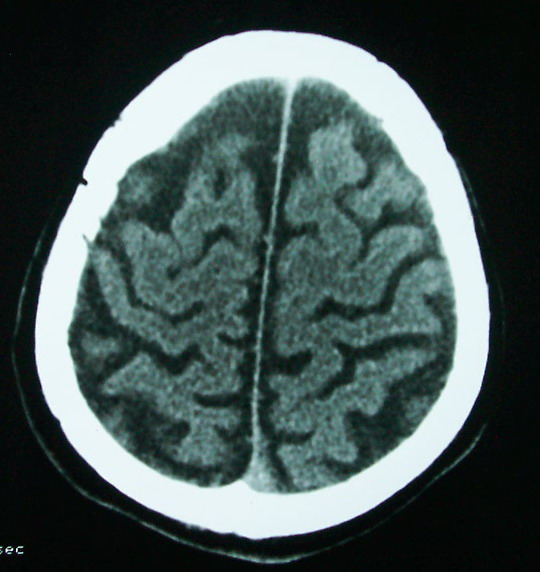

以下是引用余辉在2009-4-15 20:49:00的发言:[br]右侧病灶发生于冠状缝区,但额骨左侧鳞也有病灶,病灶区脑沟裂增宽(有脑萎缩征像,把这个征像放在颅骨病变一起考虑可能有点牵强),是否可能是板障血管畸形所致谢?抑或是嗜酸性肉芽肿或蛛网膜粒压迹那类东西?

以下是引用whzht在2009-4-15 20:57:00的发言:[br]1、额骨改变,考虑蛛网膜粒压迹;[br]2、脑萎缩。